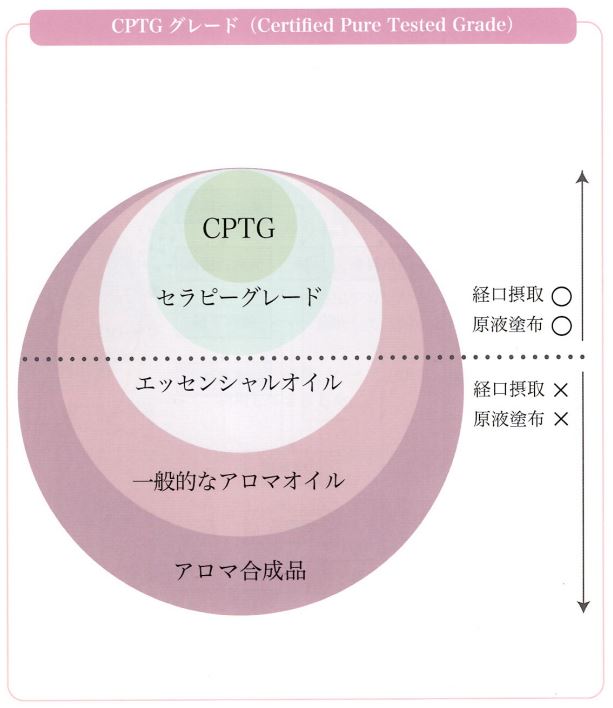

メディカルアロマ外来 2022.3.1

医療に使われるアロマを取り入れております。

フランスやベルギーでも現在、医療として使われておりアメリカでも取り入れを始めています。

市場に出回っている一般的なエッセンシャルオイルの多くはその純度が証明されていなくて、全てが安全というわけではありません。

増量剤などの添加物や農薬などの残留物、不純物が含まれていることがあります。

クリニックで取り扱っているアロマオイルはドテラ社のものでCPTG基準を満たした最高級の品質です。

経口摂取もできますし原液塗布もできます。